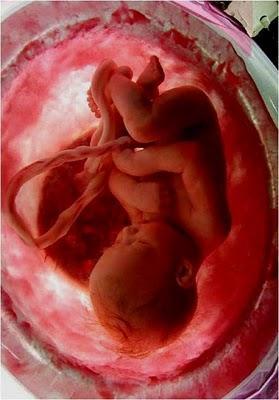

A LA 16ª SEMANA DE GESTACIÓN YA CASI TODOSSUS ÓRGANOS ESTÁN DESARROLLADOS.

LOS OJOS AÚN ESTÁN CERRADOS, SUS MANOS Y PIE COMIENZAN A MOVERSE, AUNQUE SU MADRE CASI NO LO PERCIBE AÚN.

ÉL COMPLETA 24 SEMANAS.DE SUS ÓRGANOS, SOLAMENTE LOS PULMONESNO ESTÁN COMPLETAMENTE FORMADOS.

EN ESTA ETAPA YA MUEVE SUS BRAZOS Y SUS PIERNAS, GUIÑA LOS OJOS, CHUPA SUS DEDOS E, INCLUSIVE,TIENE SUS PRIMEROS ACCESOS DE HIPO.

ESTÁ CADA VEZ MÁS CONSCIENTEDE EL ESPACIO QUE LO RODEA.

COMO TODOS LOS FETOS, PASA LA MAYOR PARTE DEL TIEMPODORMIDO Y, CUANDO DUERME, NADA CONSIGUE DESPERTARLO.LLEGA INCLUSO A SOÑAR.